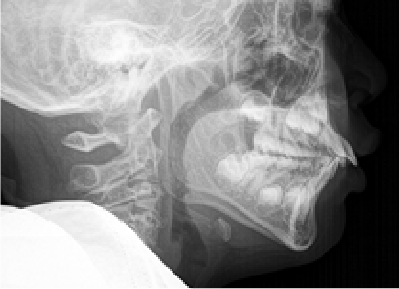

下方成長の症例のbefore/after

バイオブロック矯正は、歯だけではなく顔全体の発達に焦点を当てた矯正治療法です。顎の下方成長(顎が下へ下がるように発達すること)を防ぐことに重点を置き、正しい方向への成長を促します。顎が正しく発達することで、永久歯が生える前に、生えやすい場所に移動するため、治療期間の短縮につながります。